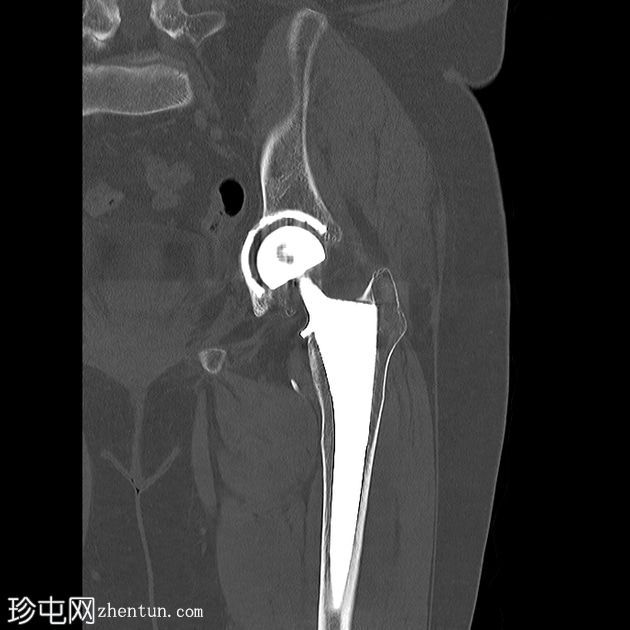

矢状位片

平扫

左侧全髋关节置换术。大转子基底部可见轻微移位的假体周围骨折。

大转子滑囊积液,可见脂肪-液体平面。

由于大多数关节置换患者为老年人,跌倒和骨质疏松的风险较高,因此假体周围骨折虽然相对少见,但仍是一种预期的并发症。

股骨大转子滑囊扩张并伴有脂肪-液体平面提示创伤性脂肪血肿。